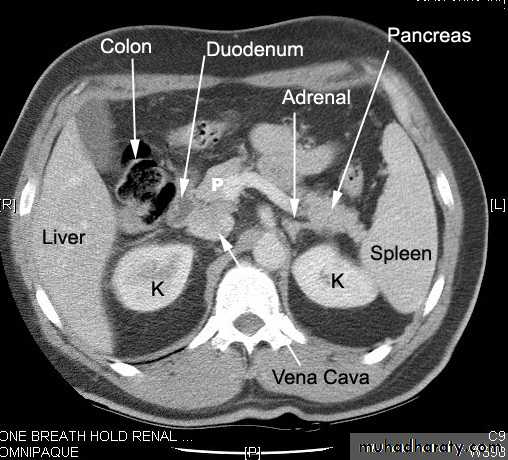

Retroperitonium

Peritoneal cavity and retroperitoneal

K: kidney